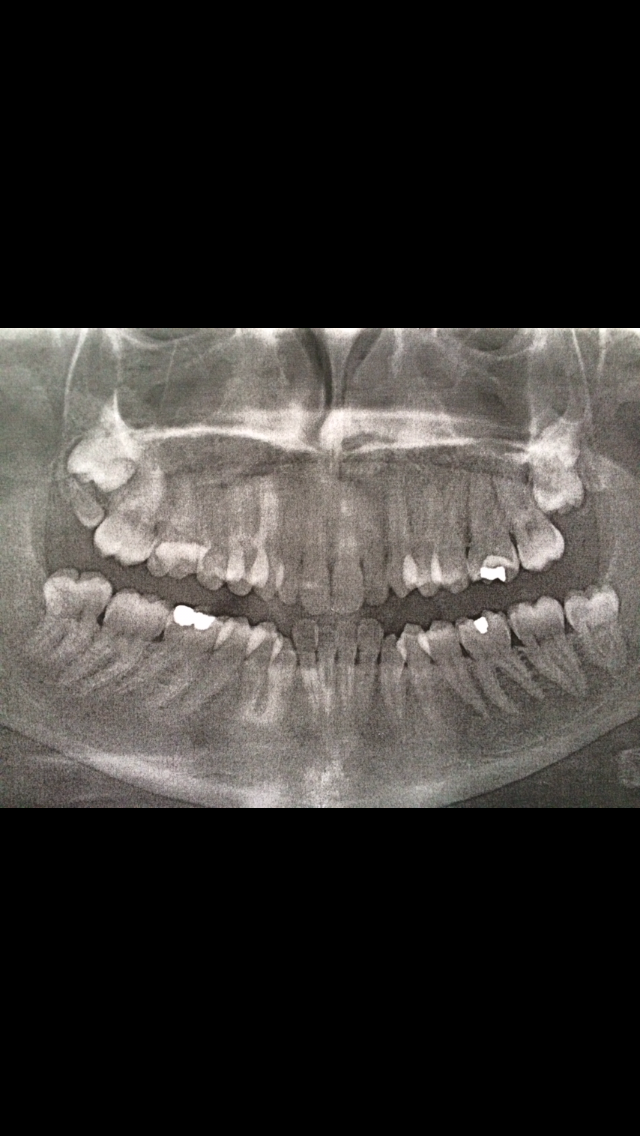

Time passed and things got worse. I’ll spare the details but I can tell you that dental pain is in a class of its own. I was popping paracetamol and ibuprofen alternately and in the haze of a painful nights sleep due to an abscess I trawled through dental phobic forums and found an actual specialist. She responded to my Sunday-4am-help-me-please-I’m-at-my-wits-end email that very morning and told me to come in the next day. She was kind. She understood the mental and psychological aspect of the phobia. She didn’t fob me off with the platitudes I’d heard before from well meaning dentists. Detailed X-rays were taken. We went through the options.

The best option was to have the two broken teeth removed. One could probably be saved but that kind of procedure is not a good idea for someone as phobic as I am. I’ve been referred to Guy’s Hospital and after going in for an initial assessment two weeks ago, I’m going in for extraction under IV sedation this Thursday.  I’ll update this post after the procedure. To say I’m scared would be an understatement. Part of me isn’t quite sure why I’ve written this but if it helps someone else understand then I suppose it was worth it. Maybe after Thursday I’ll see that it was worth it. I just hope I can get through it without another panic attack. That would be a start.